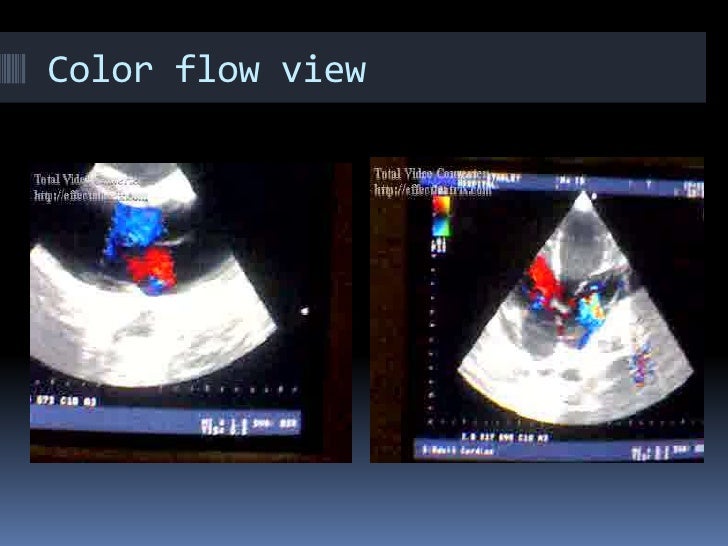

Echocardiogram Basics What Does Medical Term Echo Mean an echocardiogram, or “echo”, is a scan used to look at the heart and nearby blood vessels. An echocardiogram (echo) uses high frequency sound waves (ultrasound) to make pictures of your heart. It’s a type of ultrasound scan, which means a. what is an echocardiogram? an echocardiogram is an ultrasound to evaluate the heart's structures and direction. What Does Medical Term Echo Mean.